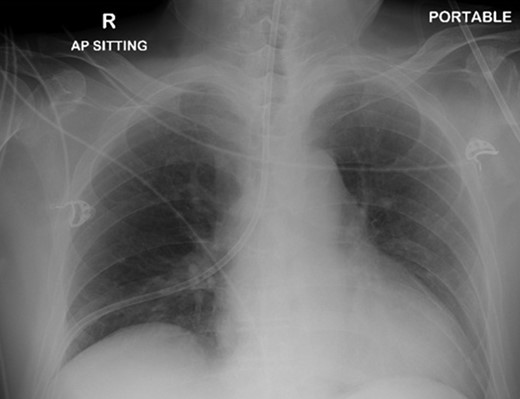

The patient was urgently reviewed by the cardiothoracic surgeons, and a small-bore chest tube was inserted, following which a computed tomography of the thorax was performed. This showed a residual but smaller pneumothorax with the chest tube in situ, associated with a small hemothorax (Fig. 3). Due to failure of conservative management and concern of a bronchopleural fistula resulting in air leak, he underwent explorative thoracoscopic surgery. Intraoperatively, an area of lung was noted with contusional changes and a bleb (Fig. 4), and a wedge resection of the right lower lobe was performed (Fig. 5). He made an uneventful recovery and was discharged.

Video assisted thoracoscopic surgery showing an area of right lung associated with a bleb and contusional changes.